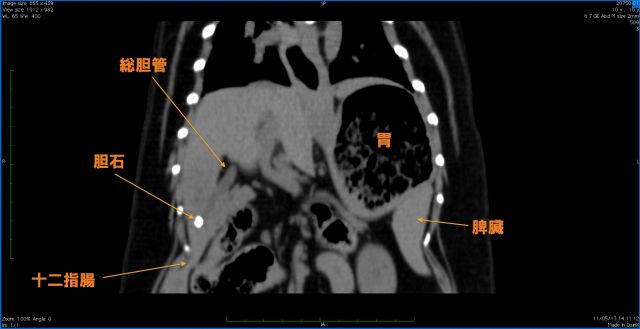

神戸大学医学部附属病院 肝胆膵外科|胆道癌・胆石症. 神戸大学医学部附属病院肝胆膵外科のページです。胆道癌とその治療法について掲載しています。.

Chclinic.Toyspa. 到診所來治療癌症腫瘤的病人可分幾種 01.怕西醫手術、化療、放療的副作用,希望僅用中醫藥治療癌症腫瘤. 神戸大学医学部附属病院 肝胆膵外科|胆道癌・胆石症. 神戸大学医学部附属病院肝胆膵外科のページです。胆道癌とその治療法について掲載しています。. 十二指腸がんの症状【十二指腸がんの警告】. 十二指腸がんの症状を徹底的に解説。十二指腸がんの症状を知りたい方は必見です。. 胰臟頭癌要切十二指腸 這手術讓她「免留30公分疤」. 89歲的呂陳老太太,因黃疸就醫後發現罹患胰臟頭癌,原本需動大手術,切除十二指腸治療,但考量病患年紀大,孝順的兒子. 蓄膿症(副鼻腔炎) 健康e聊網. 副鼻腔有四個,分別是上顎竇、篩骨竇、額竇、蝶竇(蝶竇從臉部前方看不見)。 副鼻腔罹患炎症時,粘膜會變厚,而造成聚. 胆道がん(胆管がん、胆嚢がん、十二指腸乳頭部がん). ※胆道癌診療ガイドライン:日本肝胆膵外科学会、日本がん治療学会 胆道癌診療ガイドライン作成出版委員会/編より抜粋. 十二指腸潰瘍と癌(ガン)腫瘍 喉痛. 十二指腸潰瘍と癌(ガン)腫瘍 十二指腸の症状 と病気. 十二指腸潰瘍が癌(ガン)腫瘍に変異したり移行する可能性とは. 十二指腸癌の手術後の食事内容!気をつけたい食べ物. 十二指腸癌は、多くの場合、初期症状を自覚するのが難しいとされています。腹痛、吐き気、嘔吐、下痢などの症状が.

達文西機器手臂微創手術 奇美醫療財團法人奇美醫院. 達文西介紹 醫療與人工智慧的結晶-達文西手術系統 (此項手術為自費項目) 自十八世紀以來,外科手術挽救了無數的生命. 神戸大学医学部附属病院 肝胆膵外科|胆道癌・胆石症. 神戸大学医学部附属病院肝胆膵外科のページです。胆道癌とその治療法について掲載しています。. 十二指腸癌の原因と治療法 junishityou. 関連ページ 十二指腸癌の症状は、腹痛と痛みと吐血などがあり治療は手術です 十二指腸癌のステージ毎の症状や特徴. 十二指腸潰瘍と癌(ガン)腫瘍 喉痛. 十二指腸潰瘍と癌(ガン)腫瘍 十二指腸の症状 と病気. 十二指腸潰瘍が癌(ガン)腫瘍に変異したり移行する可能性とは. 大腸癌 a+醫學百科. 此頁由A+醫學百科用戶行医於2014年7月22日 (星期二) 1830的最後更改。 在李文丰和a+醫學百科用戶医者的工作基礎上。. 胰腺癌 a+醫學百科 cht.Ahospital. 胰腺癌(cancer of pancreas,pancreatic cancer)是消化道常見的惡性腫瘤之一,多發生於胰頭部,稱為胰頭癌,也有發生在胰體的癌. 膽道癌簡介 website.Tpech.Gov.Tw. 治療 手術切除是唯一有效治療方法。如果伴隨有肝內結石,當然必須另加總膽管切開及引流。若病人有併發黃疸或膽道感染. 壺腹癌ampulla of vater cancer化學治療的選擇 胃腸道癌症 陳駿逸 醫師 話聊俱樂部. 【文 中西整合癌症治療 腫瘤 / 安寧療護西醫專科醫師 癌症中醫師 陳駿逸】 前成功大學校長吳京今 (14) 天中午左右因壺腹癌.